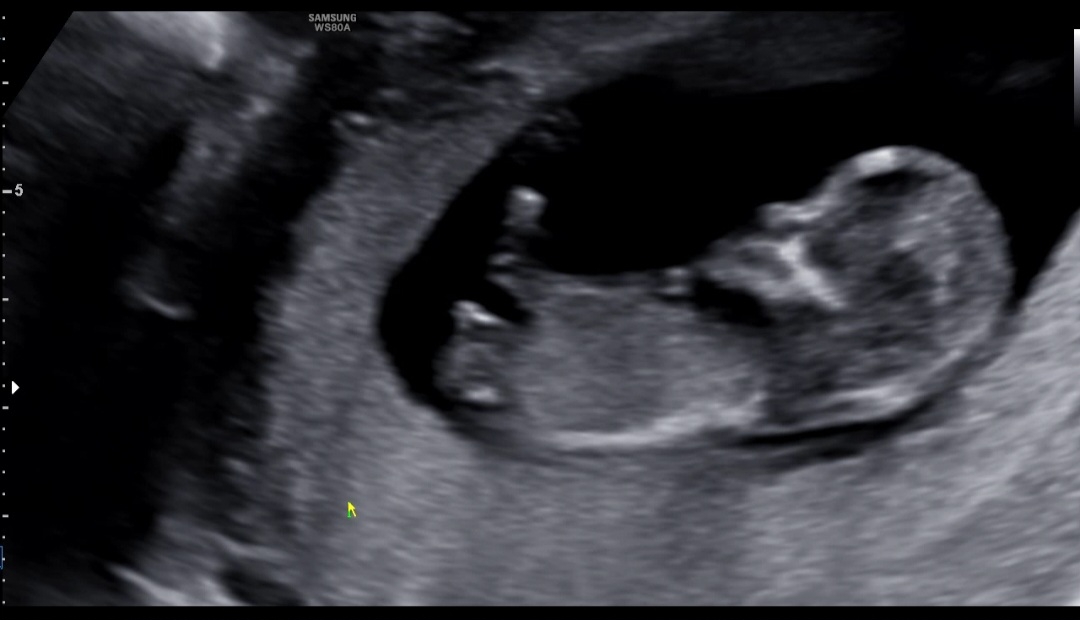

아들같아요

11주 4일차 (11주 6일 크기)인데요 딸일까요 아들일까요 병원에선 정확하지않지만 아들같다고 하시는데 딸같기도하고 애매하네요

저기 다리 사이 🌶️ 같이 보이네욤ㅋㅋ